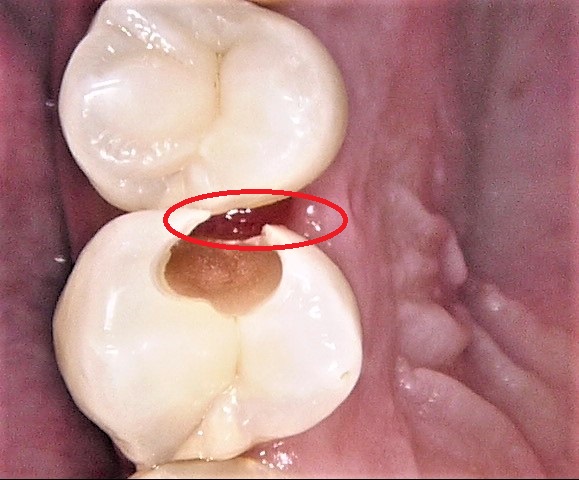

赤丸の部分の歯と歯の間には、詰まったままで取れなくなった食片(食べカス)が残っています。このまま放置すると、歯ぐきが炎症を起こして、歯周病になる可能性もあります。

食片を取り除きました。詰まっていた部分の下の歯ぐきが赤く腫れています。